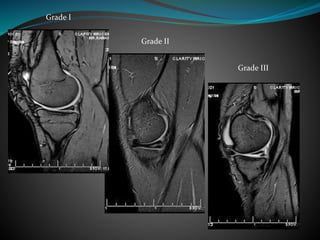

 Grade

Grade 1- Globular signal within the meniscus

Grade 2- Linear signal within the meniscus

not reaching the articular surface

Grade 3- Linear signal within the meniscus

reaching the articular surface

Grade I

Grade II

Grade III